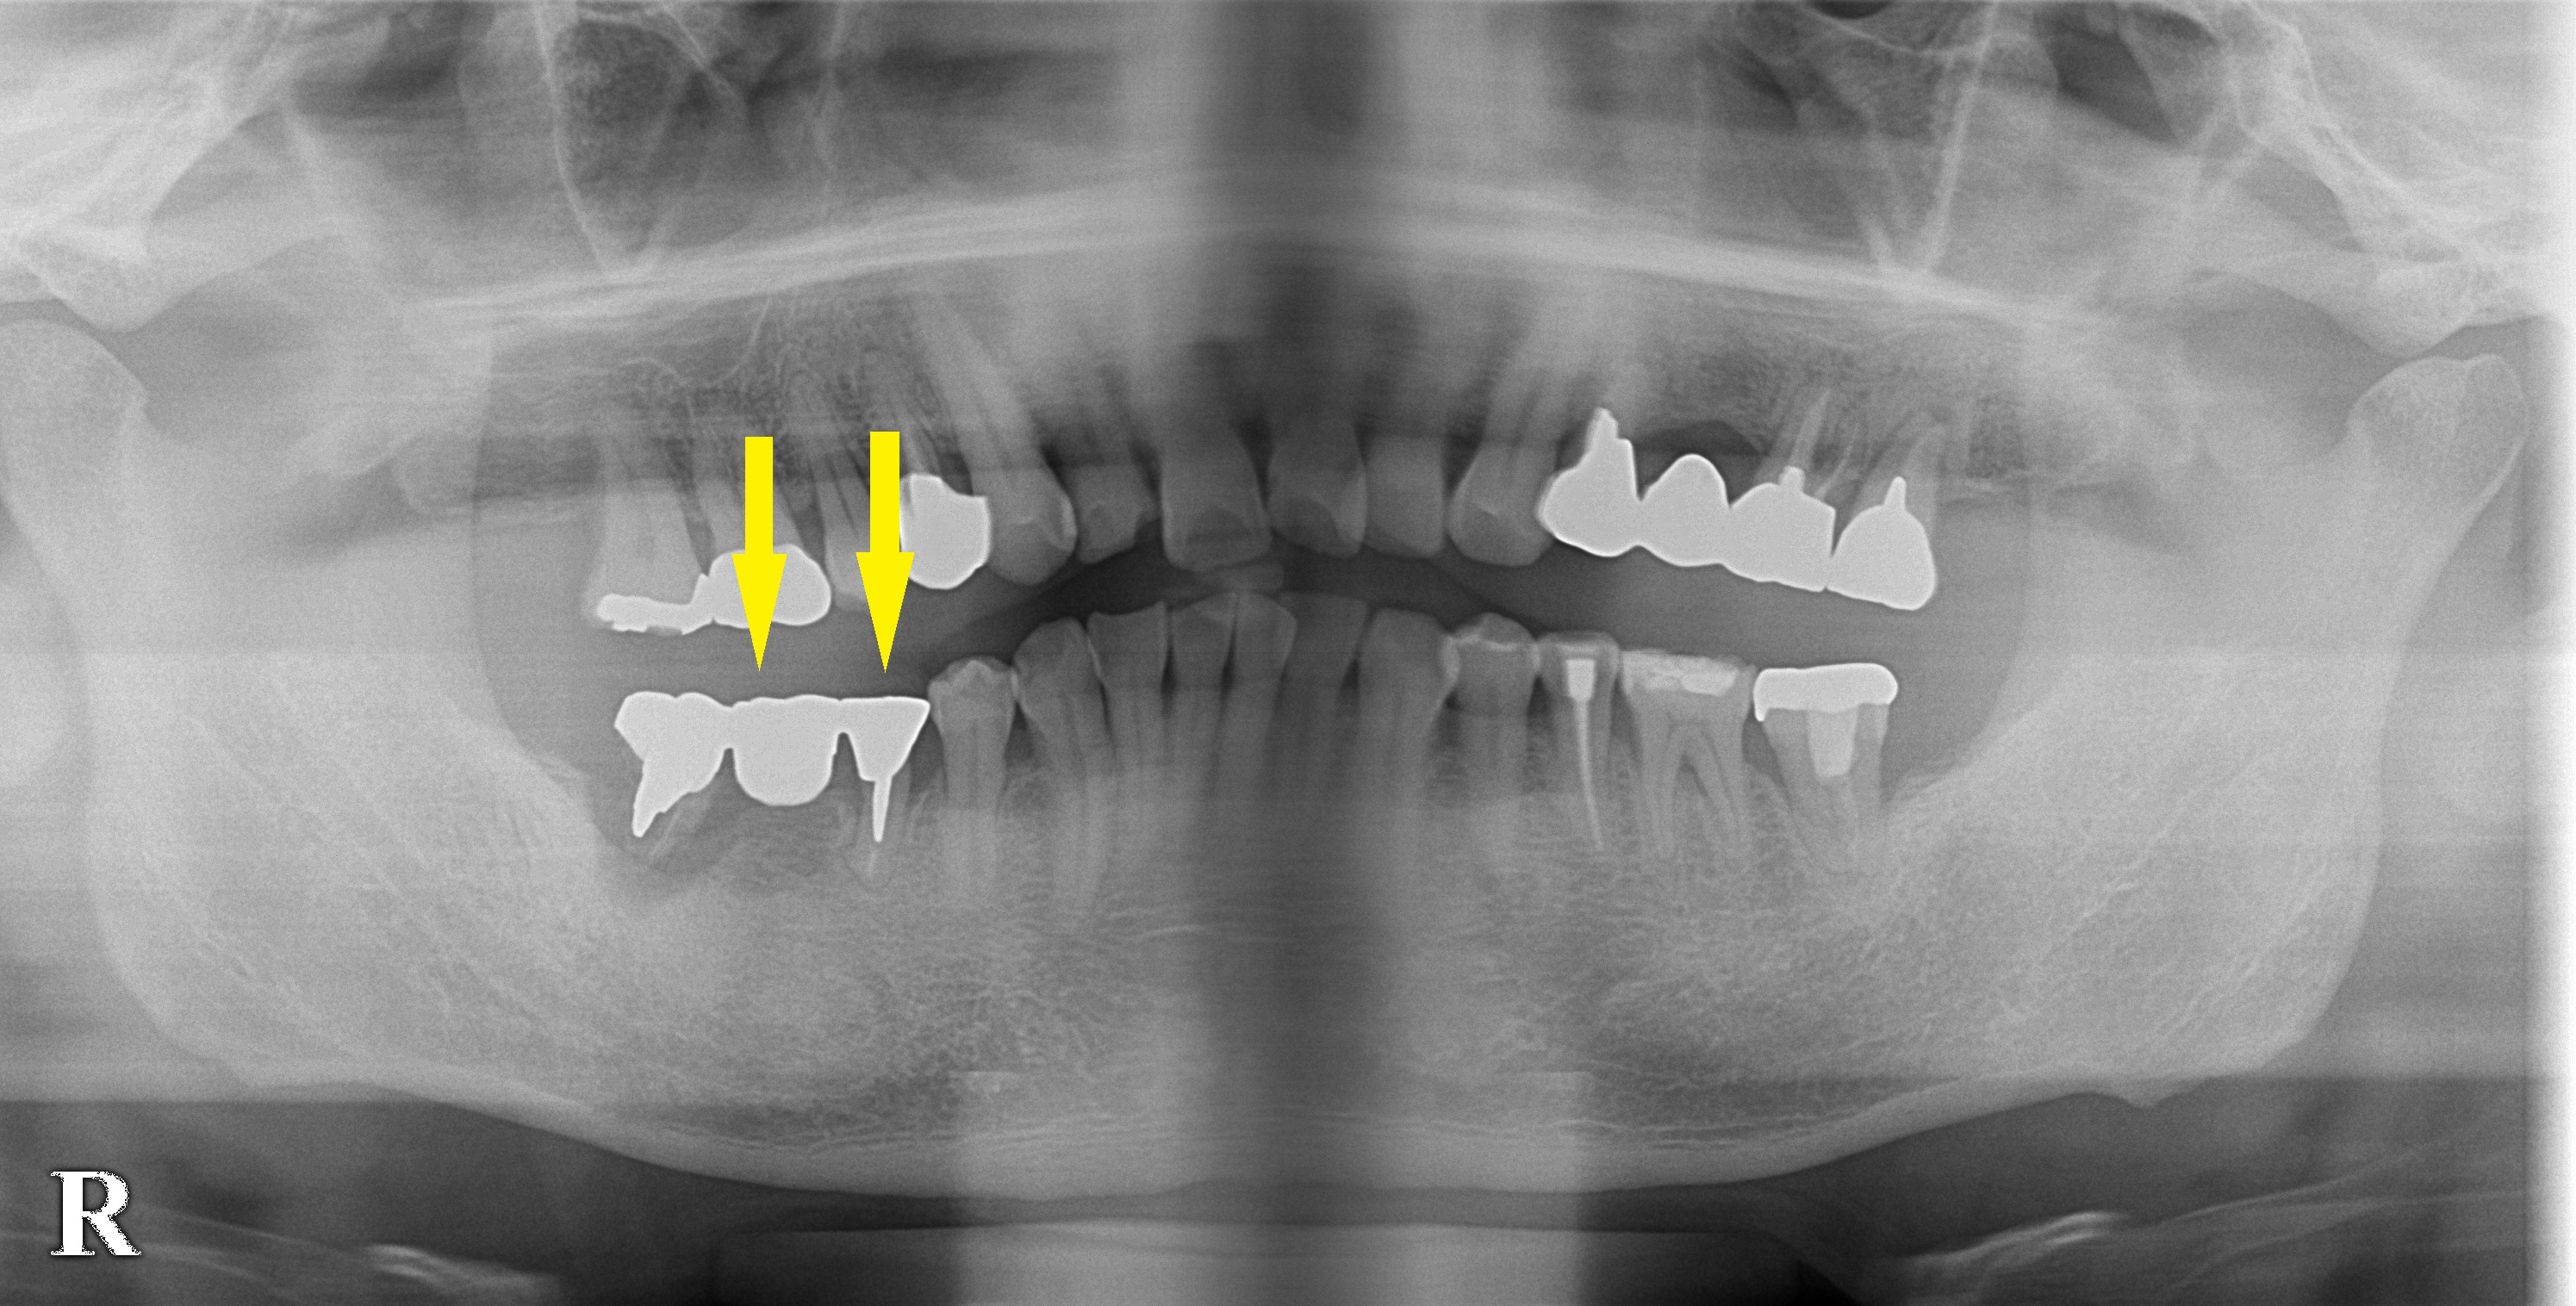

レントゲン写真で、ブリッジの後方の歯の周囲は骨が吸収され、前方の歯もかなり動揺がありました。

後方の歯は、骨吸収が大きいので、ここにはインプラントを埋入せず、ブリッジの前方の歯のところに、1本抜歯即時インプラント埋入、ブリッジのダミーの部位にもう1本埋入して、臼歯2本の回復を行うこととしました。